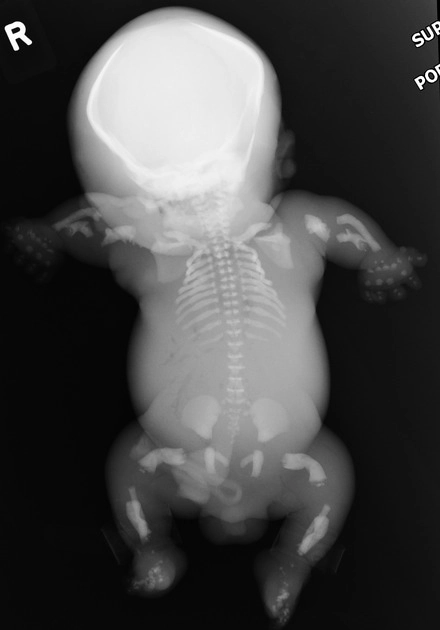

Thai vô sọ (Acrania, Exencephaly và Anencephaly)